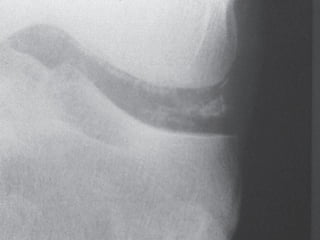

Plain Radiographs

:

Chondrocalcinosis It is classically seen in

-

Fibrocartilage (knee menisci, triangular

ligament of the wrist, symphysis pubis) →

punctate

Hyaline articular cartilage (knee, shoulder,

hip) → linear

linear

Tendon insertion sites (Achilles) → linear

Structural Joint Changes

CPPD can be associated with

subchondral sclerosis, subchondral

cyst, and joint space narrowing. Although

the findings are also seen in OA, the

location may help differentiate

.

Unlike RA, CPPD does not have typical

bony erosions

IMAGING Plain Radiographs : Chondrocalcinosis Itis classically seen in - Fibrocartilage (knee menisci, triangular ligament of the wrist, symphysis pubis) → punctate punctate - Hyaline articular cartilage (knee, shoulder, hip) → linear linear - Tendon insertion sites (Achilles) → linear - Bursa

Structural Joint Changes - CPPDcan be associated with subchondral sclerosis, subchondral cyst, and joint space narrowing. Although the findings are also seen in OA, the location may help differentiate . - Unlike RA, CPPD does not have typical bony erosions .